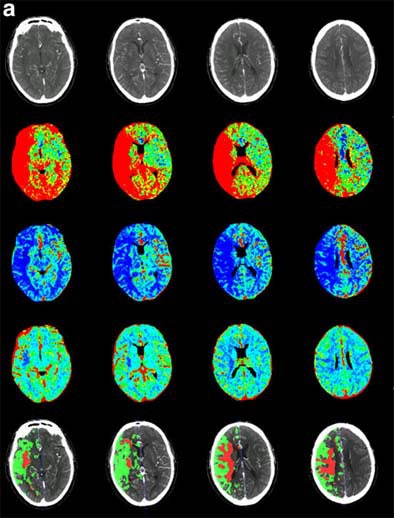

| Recent CT survey of a 62-year-old male patient admitted to our emergency room with a) left hemisyndrome, including a) perfusion CT and b-e) CT angiography (CTA). Above: From the perfusion CT raw data (first line), three parametric maps can be extracted relating to mean transit time (MTT, second line), regional cerebral blood flow (rCBF, third line) and regional cerebral blood volume (rCBV, fourth line), respectively. Applying the concept of cerebral vascular autoregulation leads to a prognostic map (fifth line), describing the infarct in red and the penumbra in green, the latter being the target of thrombolytic drugs. Below: b, c) CTA enables identification of the origin of the hemodynamic disturbance demonstrated by perfusion CT. In this patient, it relates to an occlusion at the right M1-M2 junction (arrows). d, e) Finally, CTA features bilateral calcified atheromatous plaques at both carotid bifurcations (arrowheads). Images courtesy of Dr. Max Wintermark. |